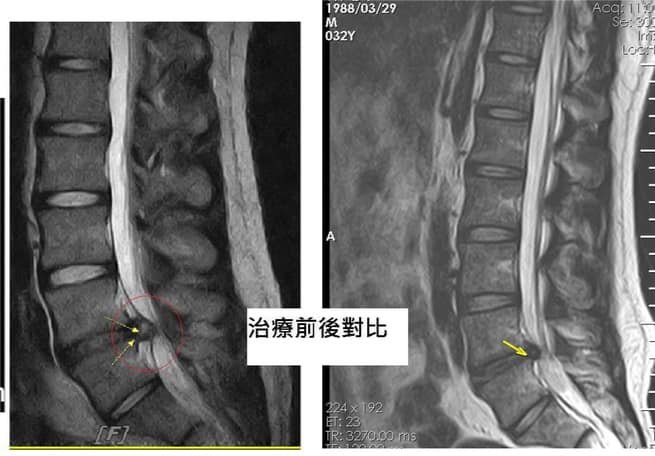

Cervical Spine Treatment Cases 腰椎治療案例 #腰椎手術失敗綜合症候群 #術後沒保養還是又繼續椎間盤突出 #感謝台北梁小姐熱情見證 ... 2021.03.02 #超感動醫案感謝中壢姚阿姨見證 #原本已經坐輪椅的人生看到一絲希望 #脊刻救援牛轉乾... 2021.02.22 #感謝新北中和區陳大哥熱情見證 #從北到南看過眾多中西醫民俗療法 #腰痛到連躺跟坐都... 2021.02.17 #感謝桃園龜山蘆先生熱情見證 #腰椎跟屁股痠痛超過十二年 #腰椎纖維環裂隙導致神經根... 2021.02.16 #騎馬摔傷腰椎醫案 #感謝內湖陳先生熱情見證 #椎間盤突出合併輕微椎間孔狹窄 #重新騎... 2021.02.03 #巨大椎間盤突出醫案 #脊椎整合中醫微創逆轉勝 #感謝三峽林先生熱情見證 #為何突出的... 2021.01.29 #腰椎粉碎性骨折手術後調養醫案 #坐輪椅的人生終於看到希望 #脊椎手術失敗症候群 #Fai... 2021.01.26 #感謝台中市大肚區患者熱情見證 #第二次治療腰痛好超多 #腰酸痛時間快一年了 #親筆寫... 2020.12.05 #腰椎嚴重滑脫醫案 #原本左腳麻痛無法久站超過十分鐘 #脊椎整合中醫微創療法逆轉勝 #... 2020.12.02 #感謝林口楊先生熱情見證 #椎間盤整和中西醫微創療法逆轉勝 #曾經大痛到無法走路嚴重... 2020.11.25 #今天來聊巨大骨刺為何可以吸收回去! #椎間盤突出需要多久才能吸收呢? #馬尾神經症候... 2020.11.10 #腰椎滑脫一定要開刀嗎? #骨科認為開刀置放骨釘穩定錐體 #如果患者可以藉由增強肌... 2020.11.04 #六年的長期腰酸痛醫案 #原來是椎管狹窄合併輕微突出 #每年冬天準時發作苦不堪言 #感... 2020.10.31 #椎管狹窄案例 #感謝新莊陳大哥熱情見證 #腰酸痛數年原來是椎管狹窄 #來診前已經痛到... 2020.10.28 #知名四代魚丸店掌門人熱情見證 #腰椎中醫微創逆轉勝 #椎間盤突出醫案 #感謝新北... 2020.10.23 ← 上一頁 8 9 10 11 12 下一頁 →